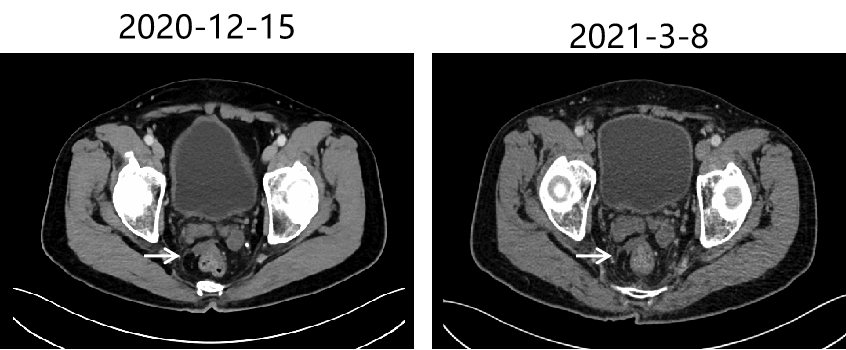

疗效评价:PR 。实体瘤临床疗效评价标准(RECIST1.1标准)

2020-12-16 18 F-FDG PET/CT提示:直肠壁未见确切异常增厚及糖代谢异常增高,盆腹部淋巴结未见增大及糖代谢异常增高;肝囊肿。

2021-3-8 复查CT提示腹膜转移病灶持续PR。